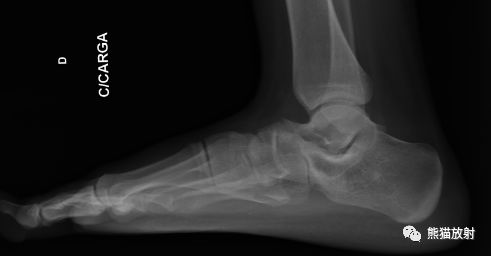

拍摄足负重正侧位,45°内斜位,跟骨轴位X线片。

8岁以前联合尚未骨化,软骨性或纤维性联合需通过其它特征诊断。

跟舟联合在侧位X线片上呈现食蚁兽鼻征,拍摄45°内斜位X片观察跟舟联合